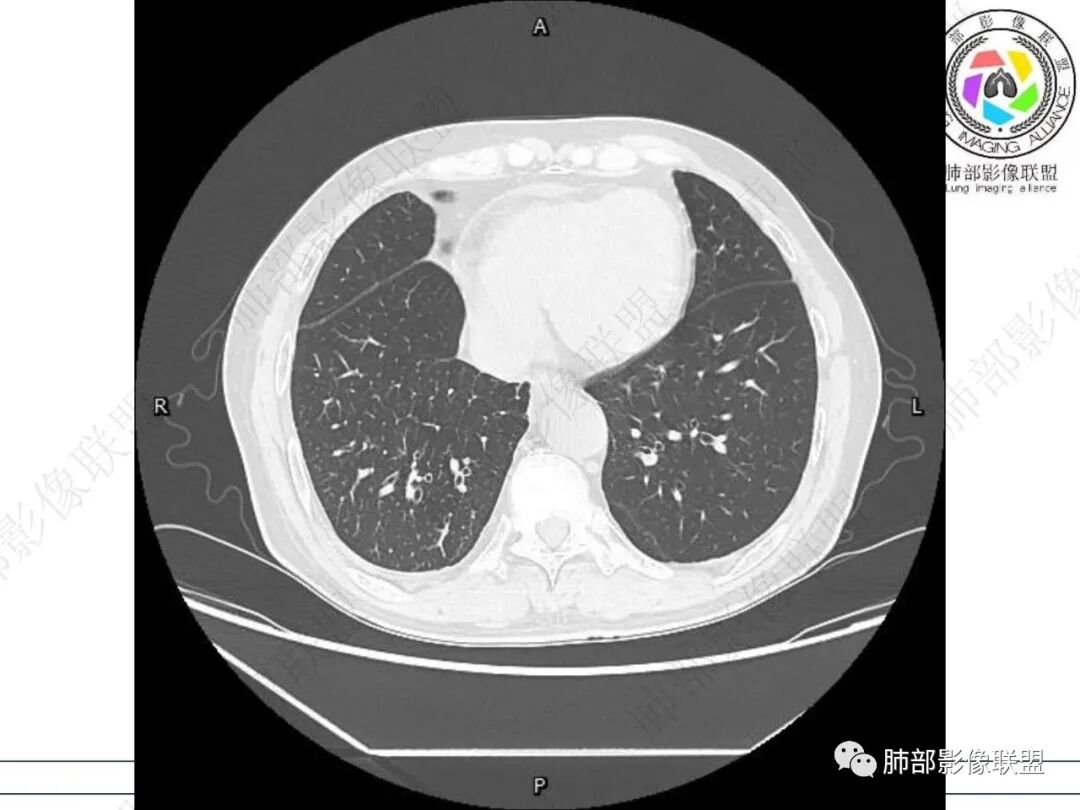

右肺下叶背段可见斑片状、条片状高密度影,支气管扩张,周围伴有磨玻璃影,边界欠清,纵隔窗:可见脊柱偏右侧可见斑片状影,与食管交界面欠清,食管形态不规则,考虑食管支气管瘘?食管异物穿孔?支气管异物?建议食管镜及支气管镜检查。

右肺下叶背段条片状实变影,内可见支气管走行,支气管有狭窄有扩张,周围可见磨玻璃影,隆突下团片影,内密度不均可见气体影,与周围结构界限不清。食管下段壁增厚,管腔狭窄,右肺下叶慢性炎、肺不张,考虑食道肿瘤所致气管食管瘘。

男,69,咳嗽咳痰10年,加重2月。ESR快。胸部CT:右肺下叶背段斑片影、条片状实变影,周围伴有磨玻璃影,边界欠清,支气管有狭窄扩张,隆突下积气团片影,与周围结构界限不清。考虑:慢性炎症致支气管-纵隔-瘘?TB?鉴别食道肿瘤致气管食管瘘。

右肺下叶沿肺叶肺段分布斑片、条片状影,以下叶背段为显,边缘模糊,内可见支气管走行,局部支气管管壁增厚,右侧胸腔少量积液。纵隔隆突下可见不均匀软组织密度影,与周围结构分界不清,内见气体密度影,与食管及相邻右肺支气管之间未显示通道。邻近食管下段壁明显不规则增厚,增强后食管管壁明显不均匀强化,可见线样强化的连续完整粘膜影。